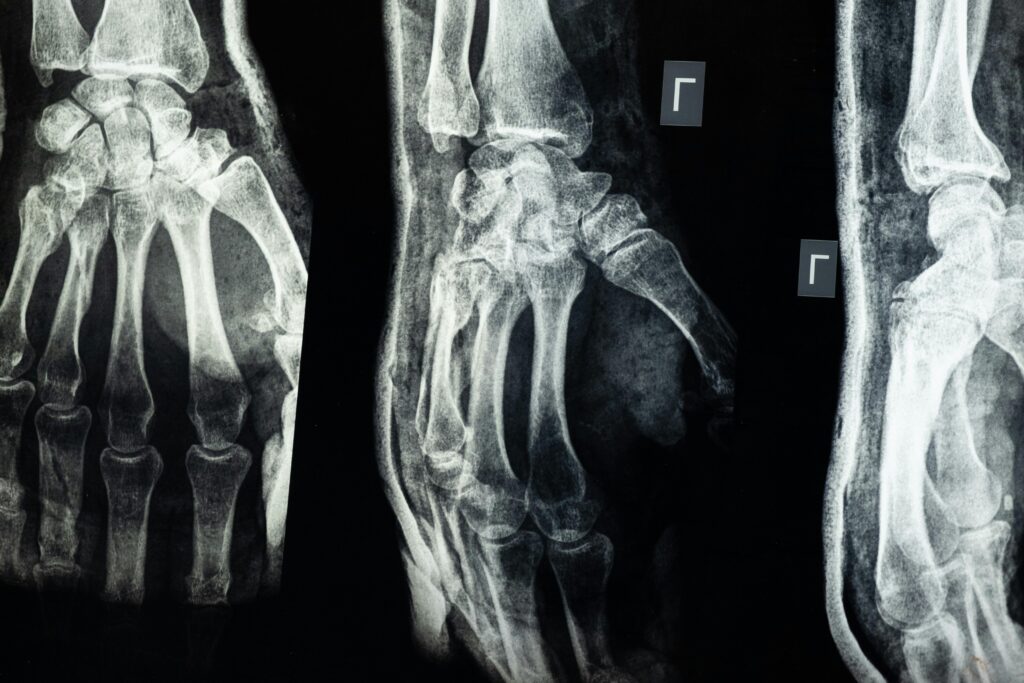

Na początek warto przyjrzeć się, ile kości posiada noworodek. Tak, rzeczywiście, noworodek ma więcej kości niż dorosły człowiek. Dokładnie mówiąc, liczba ta wynosi około 270 kości. Przyczyna tego zjawiska jest dość prosta i związana z rozwojem ciała. W momencie urodzenia, wiele kości noworodka składa się z bardziej elastycznych elementów niż u dorosłego. Są to głównie chrząstki, które z czasem ulegają kostnieniu, co umożliwia im pełnienie różnorodnych funkcji biomechanicznych.

Dzięki temu dzieci są bardziej elastyczne i odporne na złamania, ponieważ ich kości są bardziej giętkie. Ten niesamowity proces pozwala również na ich właściwe rozwijanie się i wzrost w miarę upływu lat. To wszystko sprawia, że proces rozwoju kości i szkieletu u dziecka jest fascynującym zjawiskiem będącym wynikiem sprytnego przystosowania organizmu do wymogów dorastania.

Przechodząc do dorosłości, liczba kości zmienia się i osiąga standardową ilość około 206 kości. Jak to możliwe, że tracimy aż około 64 kości? Odpowiedzią na to pytanie jest proces zwany kostnieniem. W czasie, gdy dziecko dorasta, niektóre mniejsze kości łączą się ze sobą, tworząc większe i trwałe struktury. Przykładowo, czaszka niemowlęcia składa się z kilku kości zrośniętych później w jedną solidną całość.

Ten proces zrastania kości z czasem powoduje, że do dorosłości liczymy już mniej kości. Niektóre kości, takie jak kręgi krzyżowe, zaczynają zespajać się ze sobą w późnych latach dzieciństwa, co pozwala na bardziej stabilną posturę i lepsze podtrzymywanie ciała. Właśnie te fizjologiczne przekształcenia są przyczyną, dla której dorosły człowiek posiada mniej kości niż dziecko.